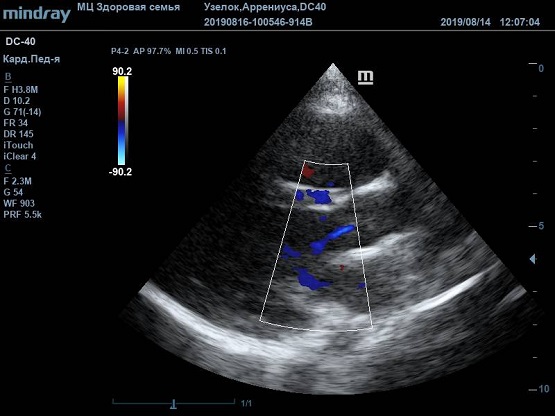

Существует вариантная анатомия, например, наросты Ламбла или гипертрофия узелков Аррениуса на полулуниях аортального клапана. Узелки и наросты увеличивают занимаемый объем полулуния, при этом нарушая конгруэнтность поверхности створок или полулуний клапана. В итоге закрытие осуществляется не полностью, и возникает легкая недостаточность. Именно такие случаи часто обнаруживаются у детей и не требуют специального лечения или пристального наблюдения.

Найти их очень просто, достаточно сечений LAXLV (длинная ось) и SAXBASE (короткая ось). Специфические крупные шаровидные структуры – узелки Аррениуса - на кончиках полулуний клапана обнаружил ультразвуковой прибор Mindray DC-40. В цветовом допплере без труда определяется аортальная регургитация легкой степени. Оценить её можно в CFM по соотношению JW/LVOT.